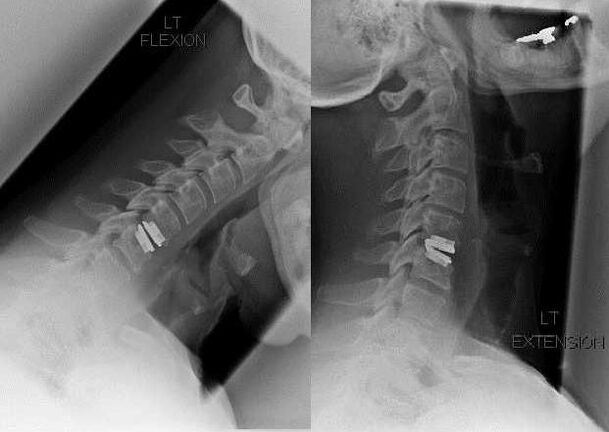

Esku-hartze kirurgikoa

Esku-hartze kirurgikorako zantzuen artean tratamendu kontserbadorea eraginkortasunik eza dago, baita zerbikaleko osteokondrosiaren konplikazioak ere, adibidez, mielopatia diskogenikoa, orno arteriaren sindromea eta sindrome erradikularra. Bizkarrezur-muina, odol-hodiak eta bizkarrezurreko sustraiak deskonprimitzeko, eragiketa hauek egiten dira:

- laminektomia;

- laminotomia;

- foraminotomia;

- facetektomia;

- diskektomia.

Kirurgia bitartean, hezur zatiak eta lotailuak kendu daitezke, eta orno arteko diskoak guztiz edo partzialki kendu daitezke. Hernial irtengune txikietarako, disko-nukleoaren laser lurrunketa egiten da askotan.

Orno-egituren eszisioaren ondoren, bizkarrezur-mugimendu-segmentuen egonkortzea eskatzen da askotan bizkarrezur-fusioaren bidez edo hezur- eta dermal-autoinjertoen instalazioak.